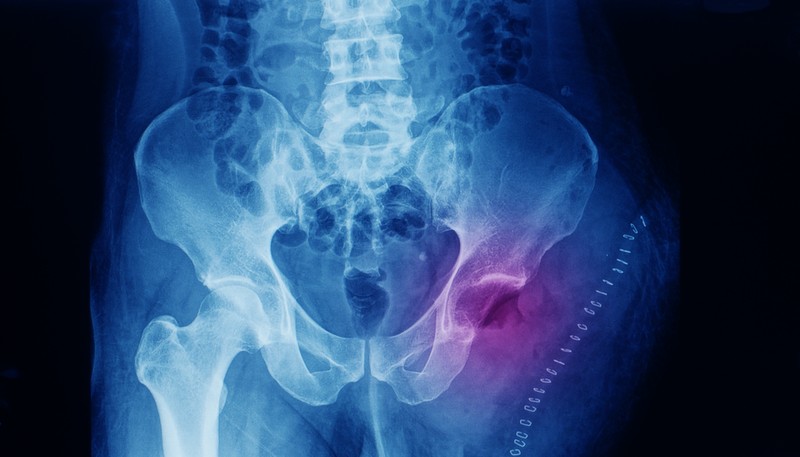

A porcsejtek rosszindulatú daganata.